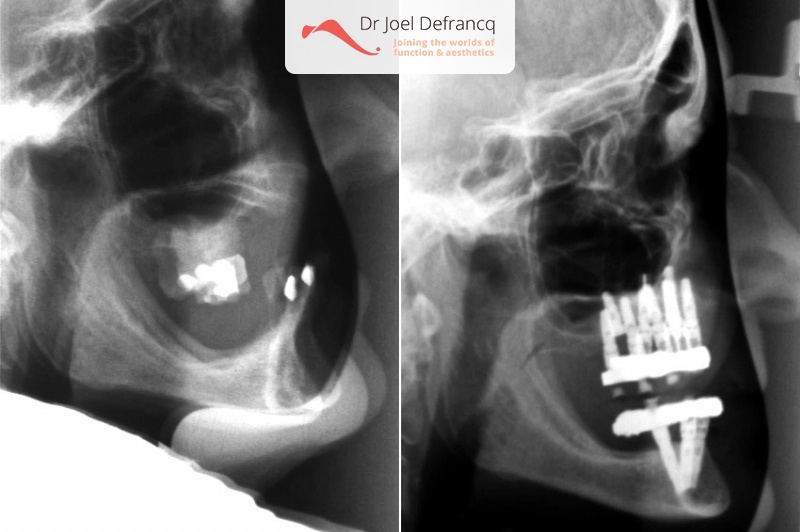

Behandeling tandheelkundige implantaten

- Vaste tanden op implantaten (bovenkaak)

- Vaste tanden op implantaten (onderkaak)

- Implantaten met beenopbouw